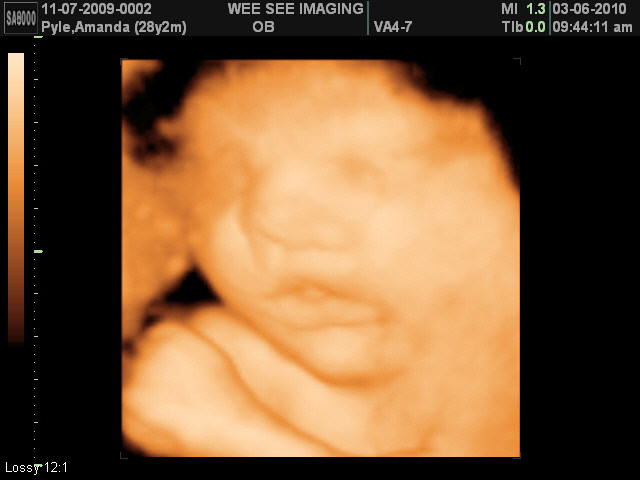

A year ago today, we were getting ready to go to Wee See for another ultrasound. I was 33 weeks pregnant, and we were beyond excited to see what our little girl looked like.

This is what we saw:

Sweet chubby cheeks with delicious lips:)

A silly baby!

A thumb sucker?

A little bit of attitude?

A happy, happy girl!

A angel sent to us from God!